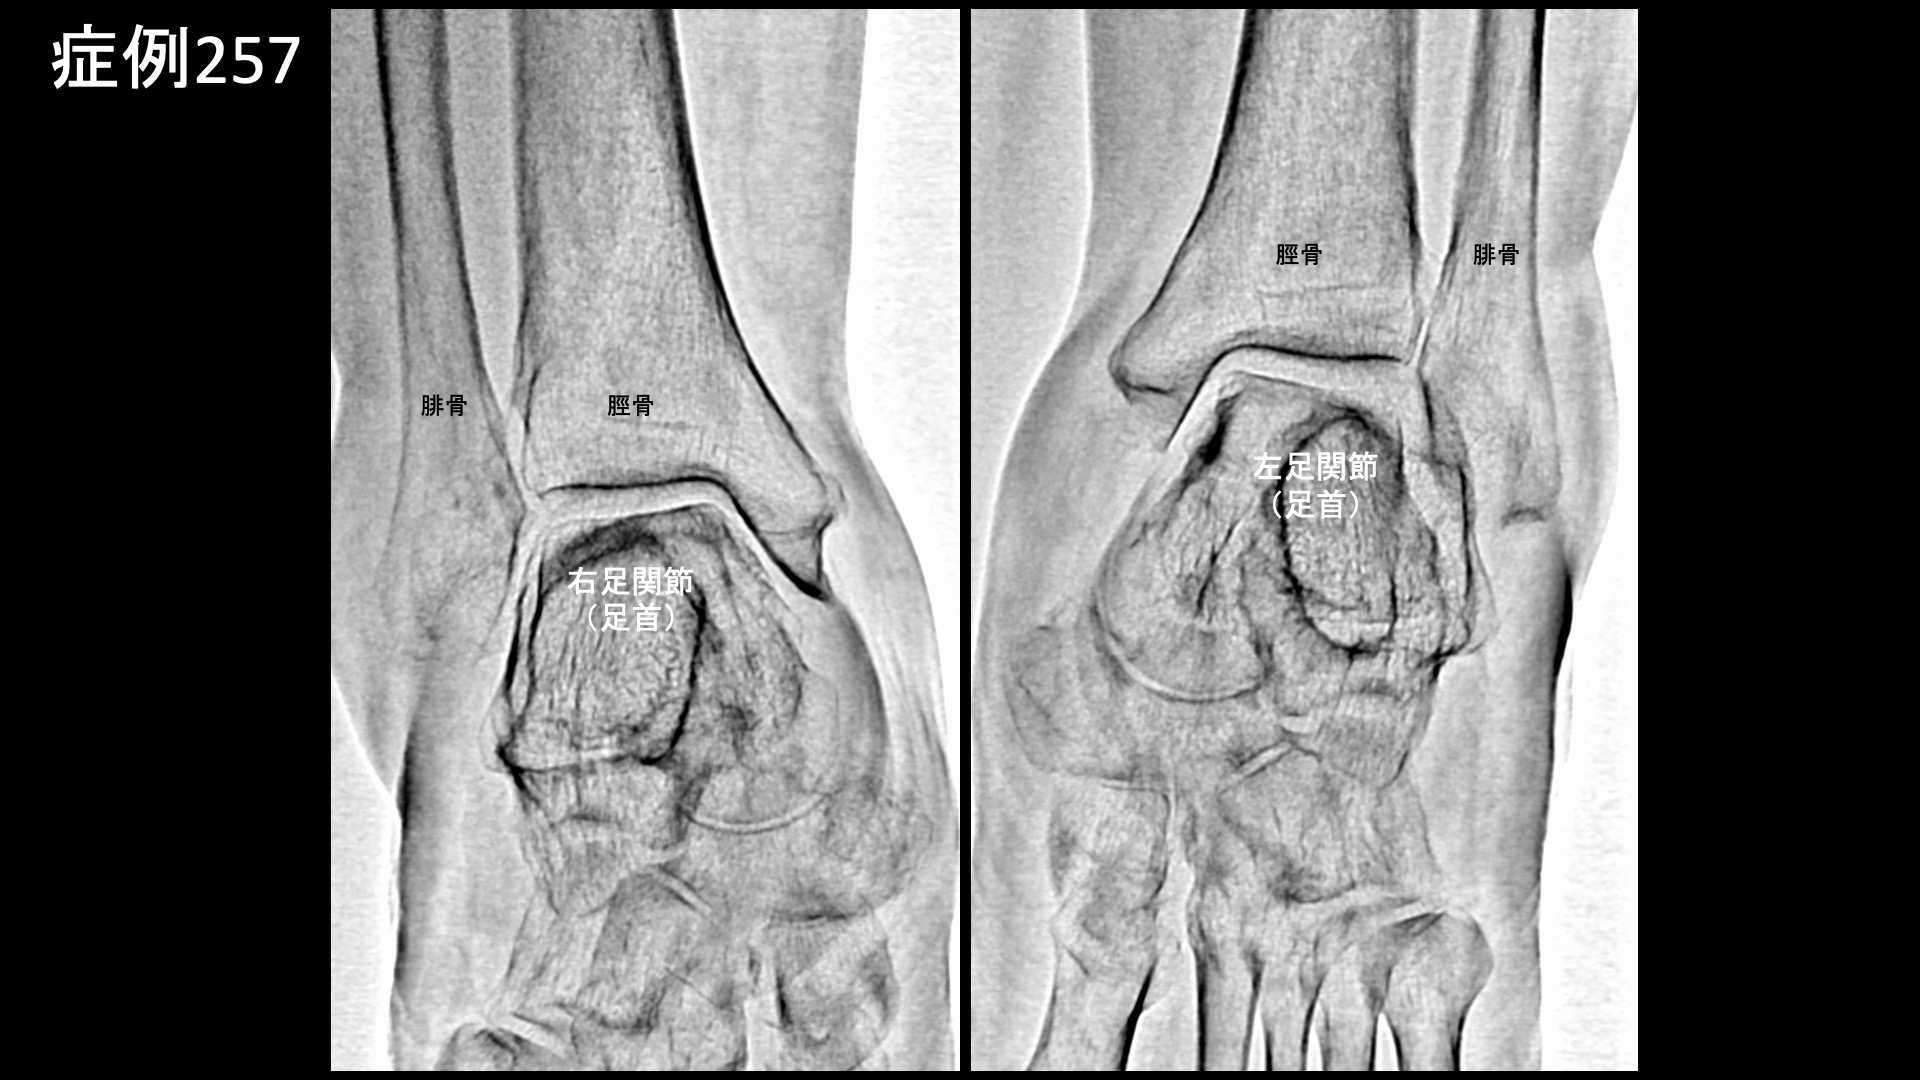

エコー検査では両膝とも水が溜まっており、モヤモヤ血管を反映した異常血流信号も内外にみられました。レントゲン検査では、両膝とも進行性の関節変形(KL分類3程度)を認めたほか、両足関節にも中等度の変形性変化を、足部では扁平足および踵骨棘を認めました。

まず膝の治療から始めました。血管造影を行うと、全ての血管でモヤモヤ血管(病的新生血管)が造影剤の濃染像として描出されました。写真では、外側上膝動脈、下行膝動脈の造影所見を示しています。典型的な変形性膝関節症の所見です。治療後、モヤモヤ血管は画像上速やかに消失しました。続いて両足首および左踵の治療です。足関節は膝と比べると、ある程度重症度が増してこなければモヤモヤ血管が明確には描出されにくい部位ですが、本症例では主要3血管(前脛骨動脈、後脛骨動脈および腓骨動脈)の全てにおいてモヤモヤ血管が認められました。左足では、さらに踵骨棘近傍にも明瞭に描出されました。滞りなく治療を行い終了しました。